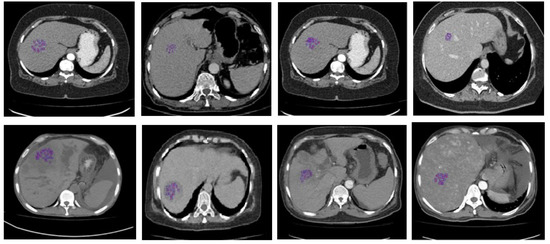

Figure 2.

Construction of ROIs for the conventional machine learning methodology. Column 1: CT image of a normal class 1 liver versus an infected liver; column 2: CT image of a normal class 2 liver versus a metastatic liver, column 3: CT image of a normal class 3 liver versus a metastatic liver; column 4: CT image of a normal class 4 liver versus an abnormal vascular area in the liver.